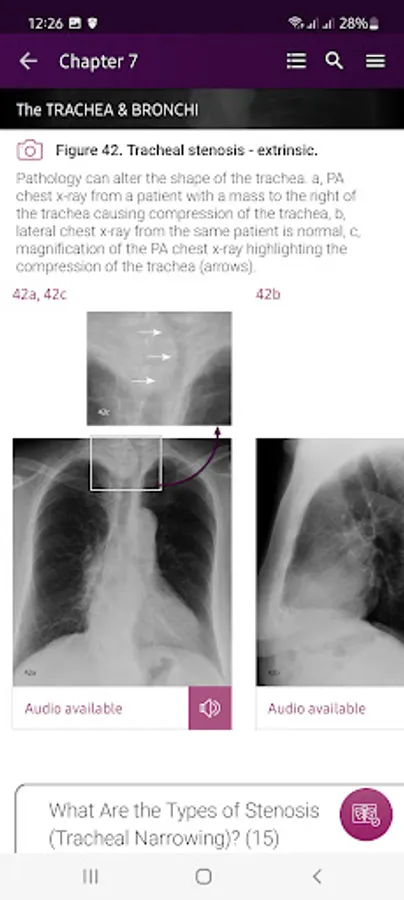

Section II* introduces the concept of radiological zones to give you a starting point in the understanding of the radiological anatomy of the chest. The next chapters review in detail the radiological anatomy of specific anatomical structures, also provide examples of how the x-ray image can change due to pathology. The final chapter explains how the individual structures come together to form the radiological image.

Pathology – Numerous interesting examples of pathology related to specific anatomical structures and regions.